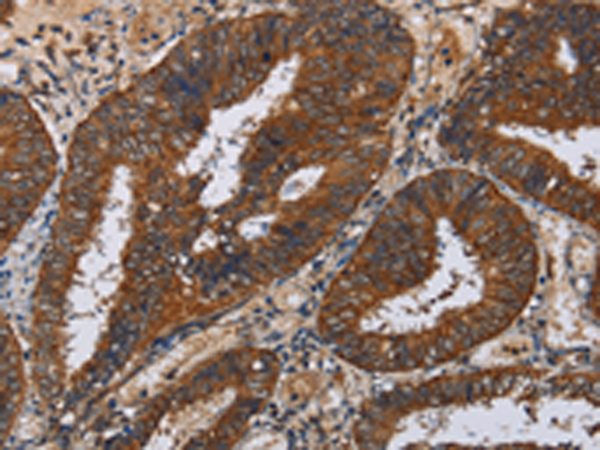

分类: 科研抗体货号: P08443别名:应用: IHC反应种属: Human, Mouse, Rat